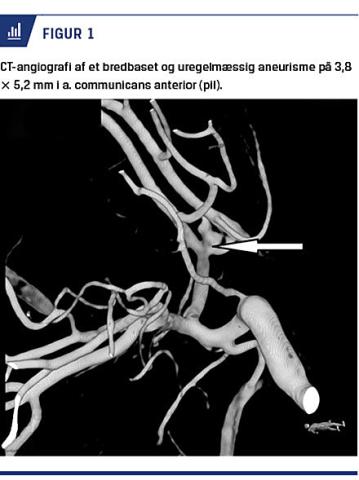

Pga. den atypiske sygehistorie og de normale blodprøveresultater udførte man CT-C for at udelukke anden årsag til kramperne. Denne viste overraskende, at patienten havde en subaraknoidalblødning (SAH) med blod i de basale cisterner og i fjerde ventrikel. Ved en efterfølgende CT-angiografi fandt man et bredbaset og uregelmæssigt aneurisme på 3,8 × 5,2 mm i a. communicans anterior (Figur 1).

Patienten blev herefter overflyttet akut til neurokirurgisk afdeling til videre behandling. Senere samme dag blev der foretaget ukompliceret coiling af aneurismet for herved at reducere risikoen for reblødning.